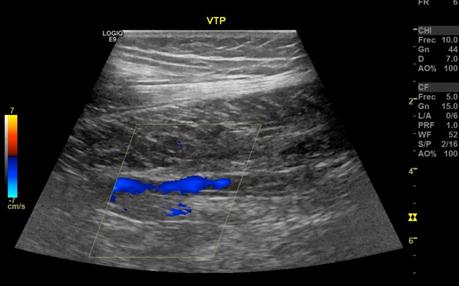

Las venas tibiales anterior, posterior y peroneas sin evidencia de alteraciones, con adecuado llenado de señal color, sin alteraciones a las maniobras de esfuerzo, con adecuada respuesta a la maniobra de aumento.